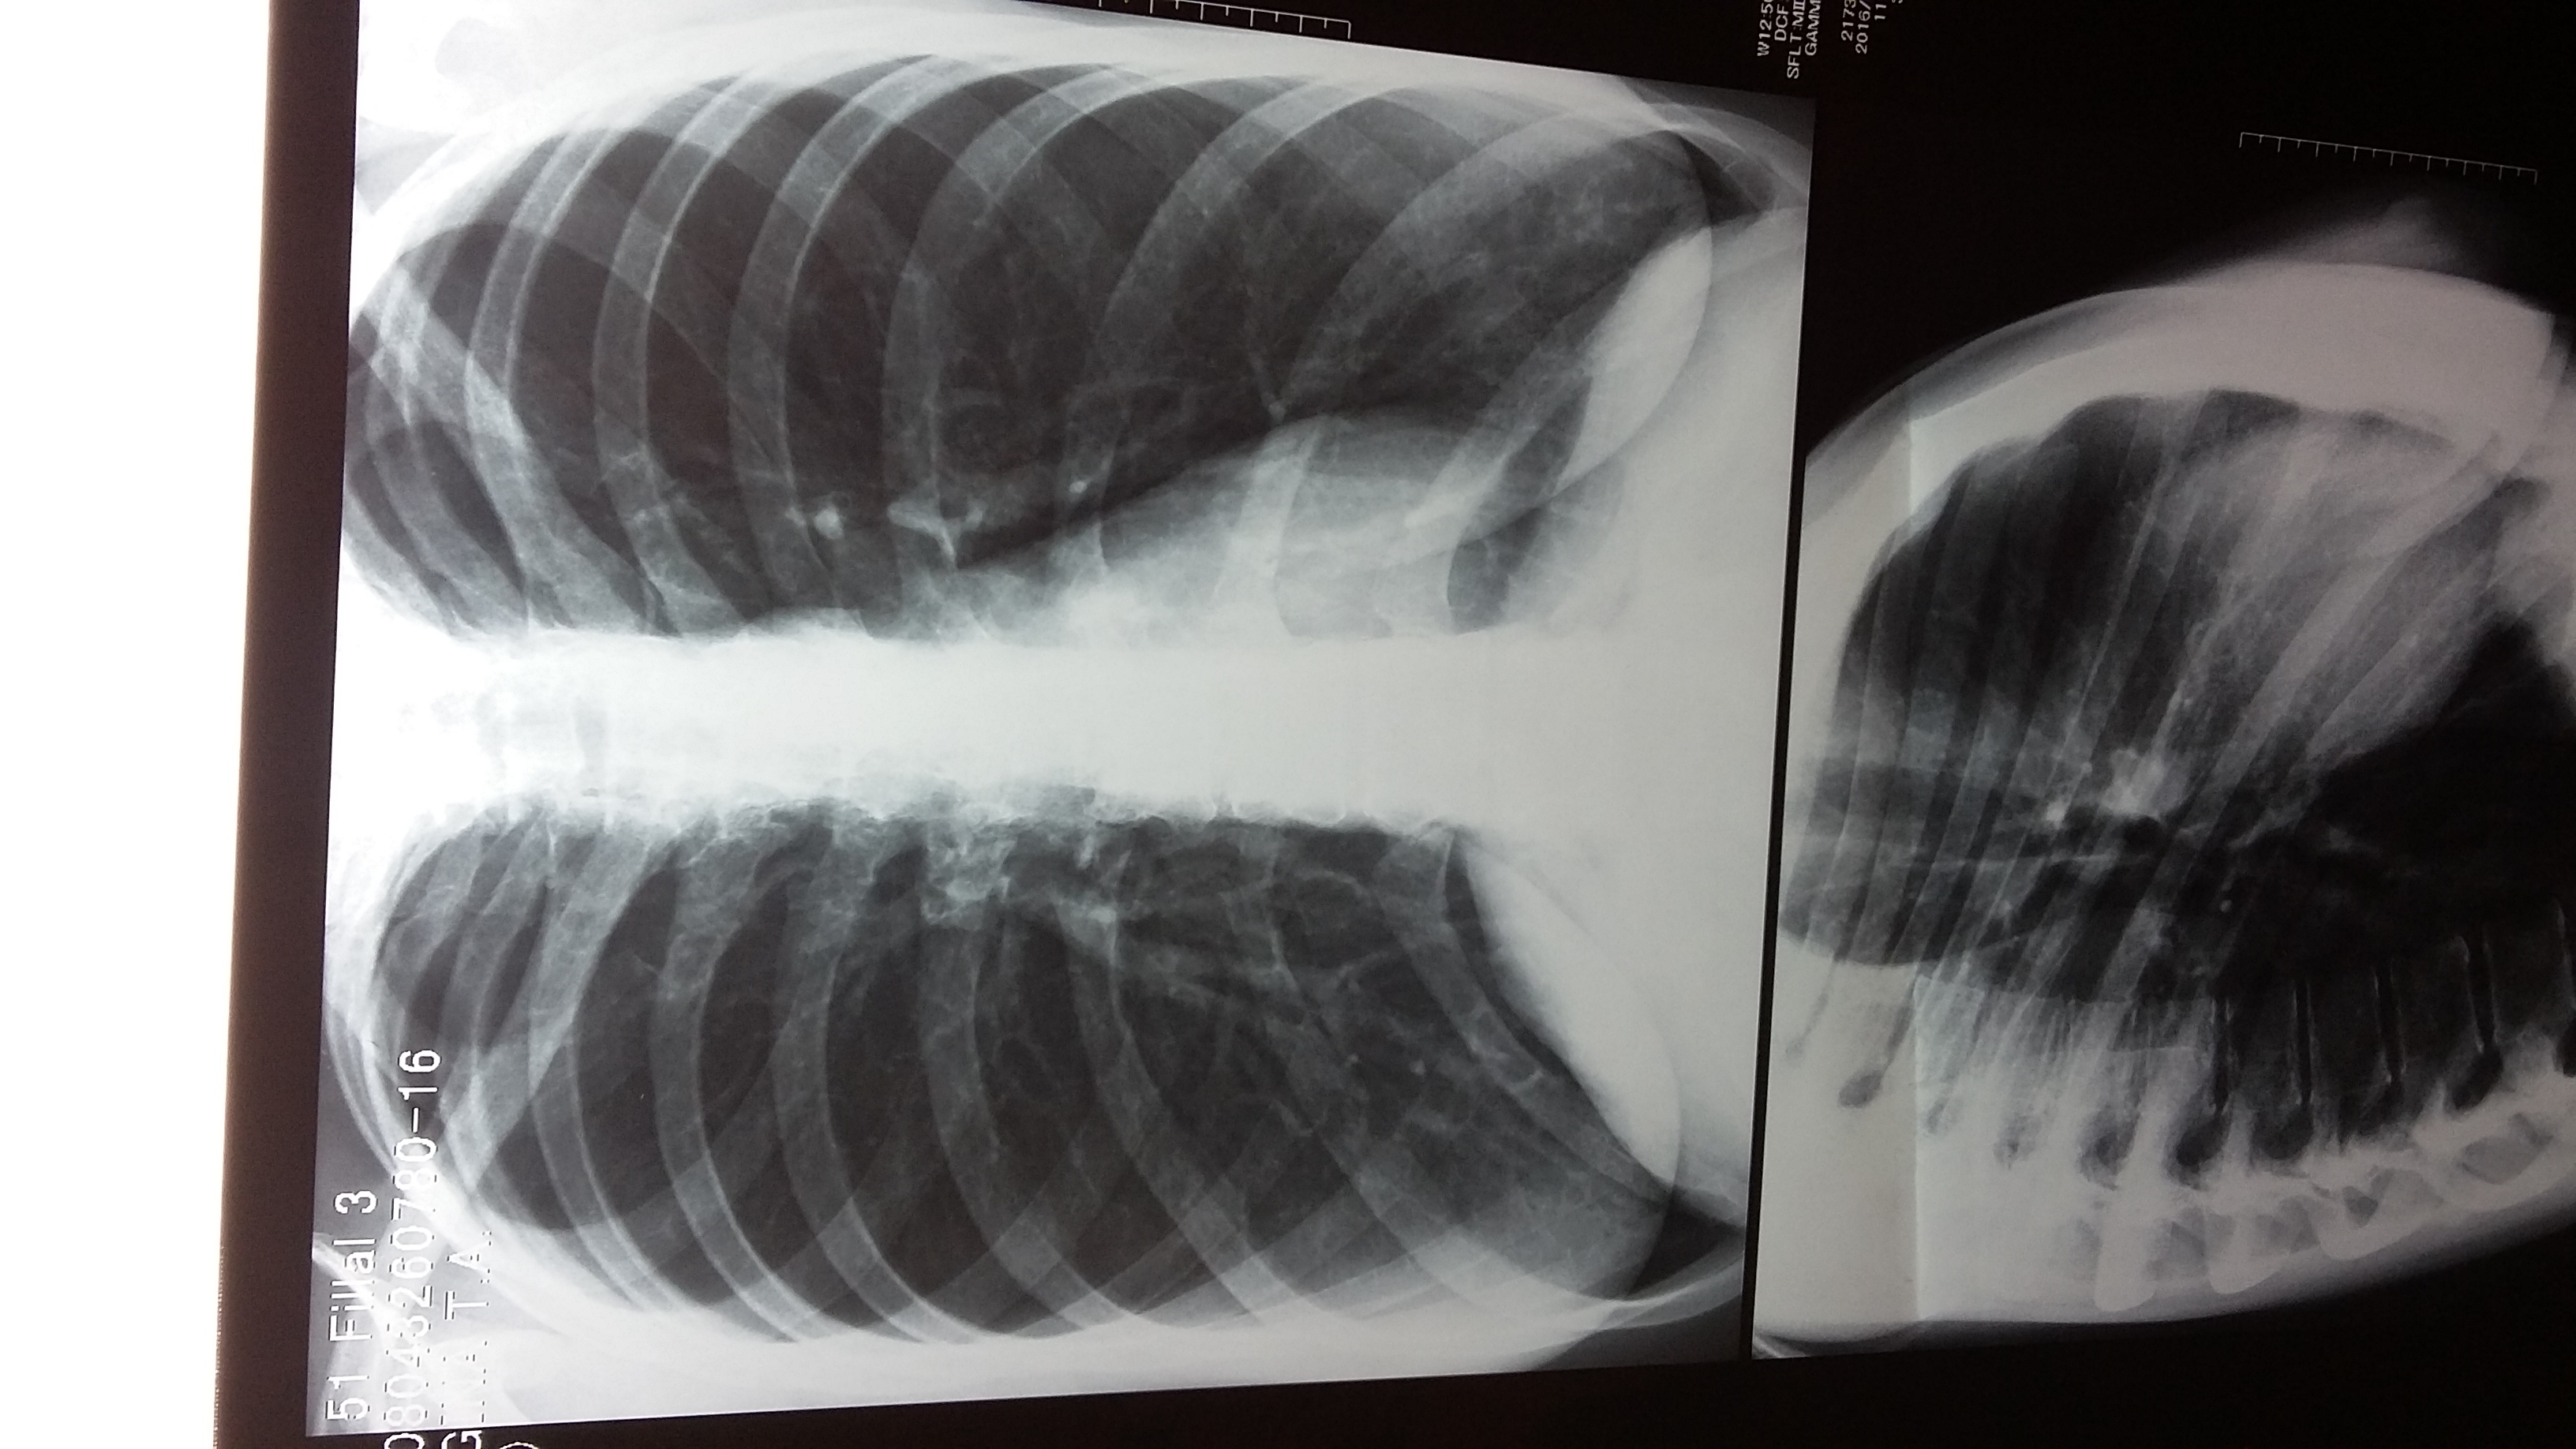

Рентгеновские снимки при пневмоцистной пневмонии